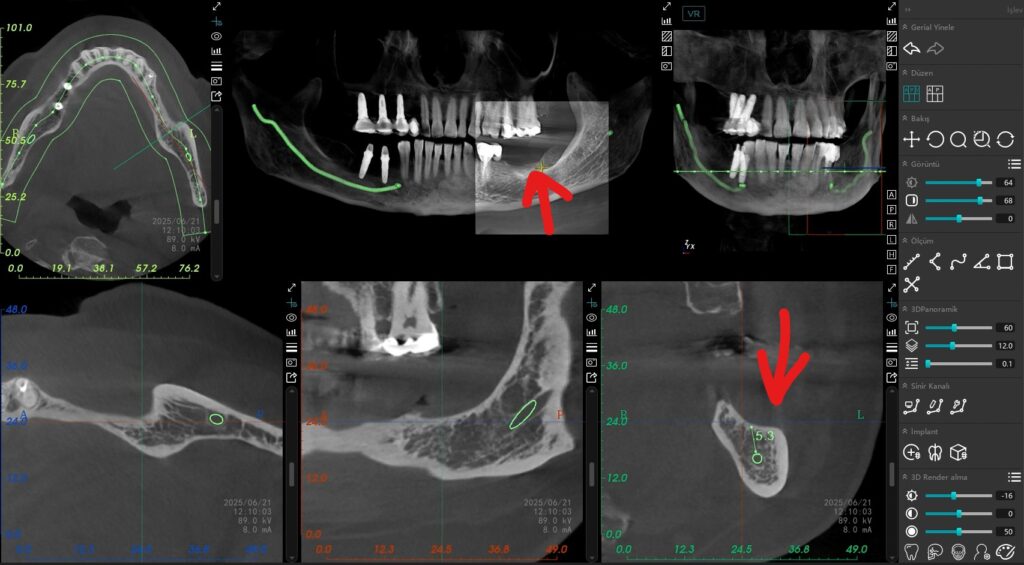

Alt çenede ana sinir kanalına olan mesafe kısıtlı (5-6 mm) olduğunda, geleneksel uzun implantlar büyük bir risk teşkil eder. Bu vakada, Alman mühendisliğinin güvenilir çözümü olan Bredent short (kısa) implantları tercih ettim. Bu özel tasarım implantlar sayesinde, sinir kanalına güvenli bir mesafede kalarak, hastamızı olası bir his kaybı riskinden tamamen korumuş olduk.